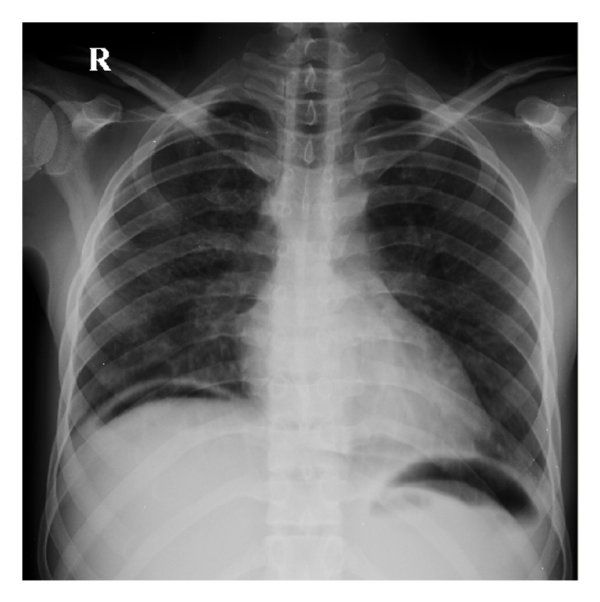

Q.5. What's the CXR finding?

Correct Answer : C